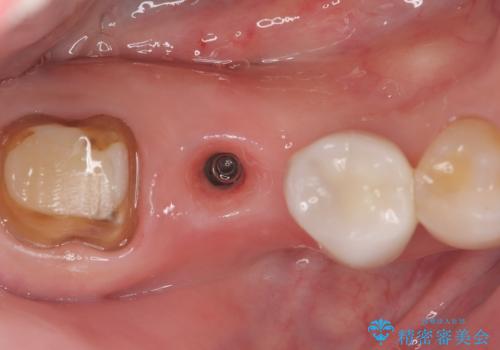

- 主訴:右下のセラミックのブリッジが何度も同じところで折れて壊れてしまう。

対合歯との咬合関係において、右下7番目と6番目の被せものの連結部がたわみやすい環境にあったため、ブリッジの新製ではなくインプラント治療を行いすべての歯を単冠仕上げとすることにしました。

何度も右下6、7間でブリッジが折れてしまうとのことでした。対合歯とブリッジの連結部が強く当たりたわみやすい状態でした。破折しずらい金属を使用したブリッジの選択もありましたが、支台歯(右下7)が失活歯場合、破折リスクが高く、破折してしまった場合にまたブリッジを外しての再治療になってしまう可能性を説明したところ、全て単冠仕上げとできるインプラント治療を希望されました。

右下5番のクラウンは、ブリッジを切断しそのまま使用していただいています。